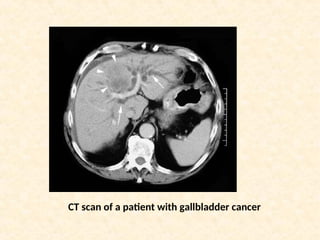

CT scan of a patient with gallbladder cancer

CT scan ofa patient with gallbladder cancer